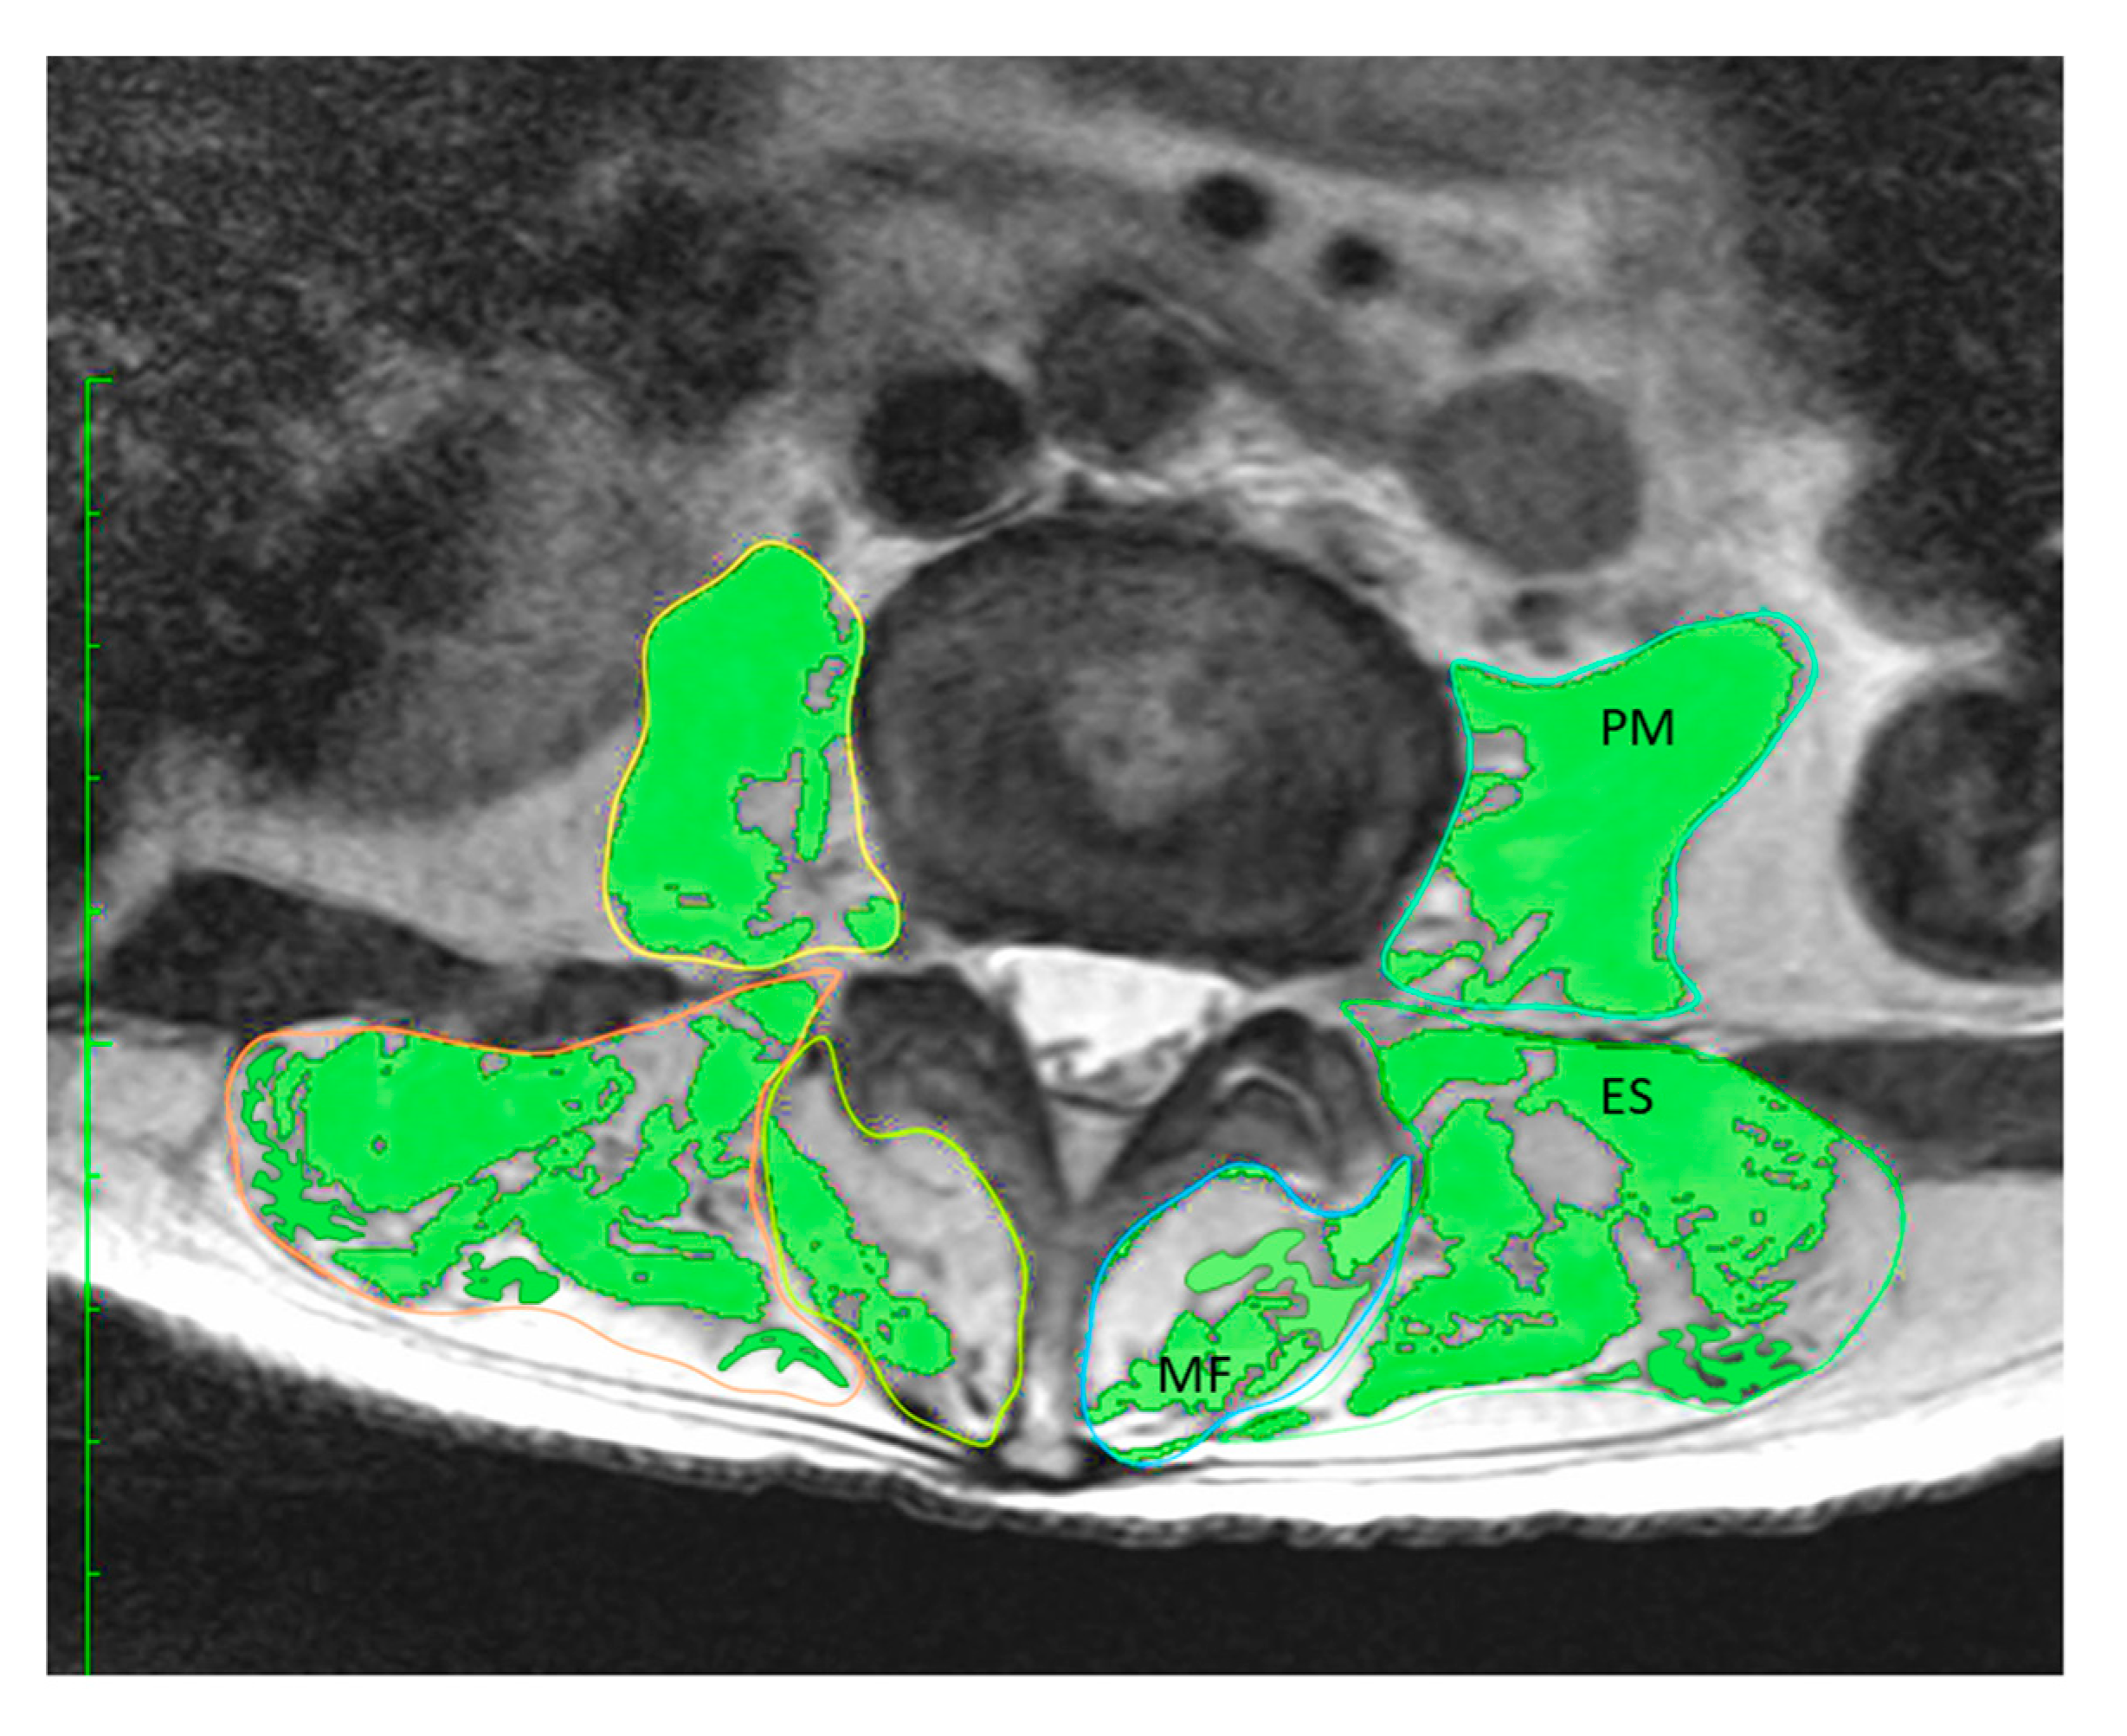

2.3.2. Quantitative Evaluation of Trunk Muscle on MRI

| ES | 28.26 (6.36) | 0.554 | <0.01 |

| ES (excluding intramuscular fat) | 23.25 (6.22) | 0.658 | <0.01 |

| MF | 8.93 (2.40) | 0.439 | <0.01 |

| MF (excluding intramuscular fat) | 6.27 (2.48) | 0.571 | <0.01 |

| PM | 16.29 (5.38) | 0.752 | <0.01 |

| PM (excluding intramuscular fat) | 15.17 (5.39) | 0.766 | <0.01 |

| Total PVM | 54.54 (11.56) | 0.746 | <0.01 |

| Total PVM (excluding intramuscular fat) | 44.70 (11.95) | 0.807 | <0.01 |